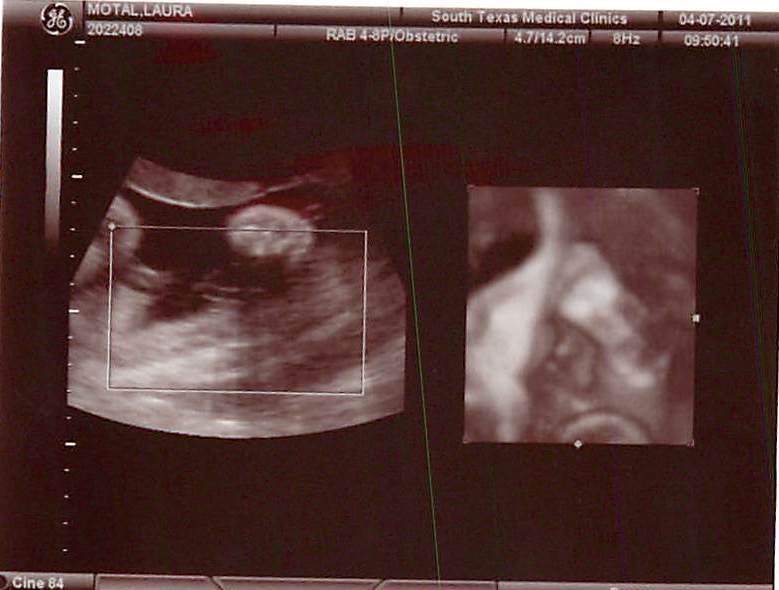

32 Week Pics

Here our Maggie's 32 week ultrasound pics.....

Here is a side view.....

Here is a 3D of the bottom of her foot....the pic on the right....

Here is a pic of her doing her high-kick!

So last Thursday we had our 32 week appointment and ultrasound. It was super exciting getting to see Maggie! I hadn't seen her since Jan. 3, and my has she grown! First the tech measured everything as normal and said all looked great! Then she switched over to 3D so we could see our little princess' face. However, it didn't work out so great. I apparently I have a ???? placenta (can't remember) but it's backwards so that makes it hard to "see" through. On top of that, Maggie was doing a high kick and blocking her face. Therefore the tech couldn't see through my placenta nor Maggie's leg. I was a little disappointed, but Jackson didn't want to see her face, so at least he will get one surprise from this pregnancy! :)